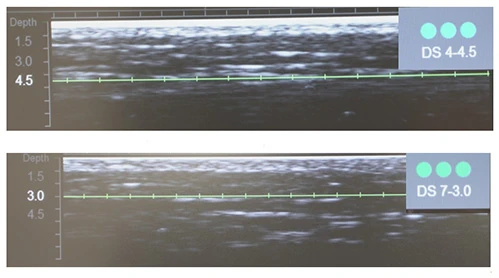

Диагностическая визуализация щечной зоны. Протокол лечения, все лицо: DS 4–4,5 80 линий; DS 7–3,0 306 линий.

Диагностическая визуализация субментальной зоны. Протокол лечения: DS 4–4,5116 линий; DS 7–3,0 112 линий .